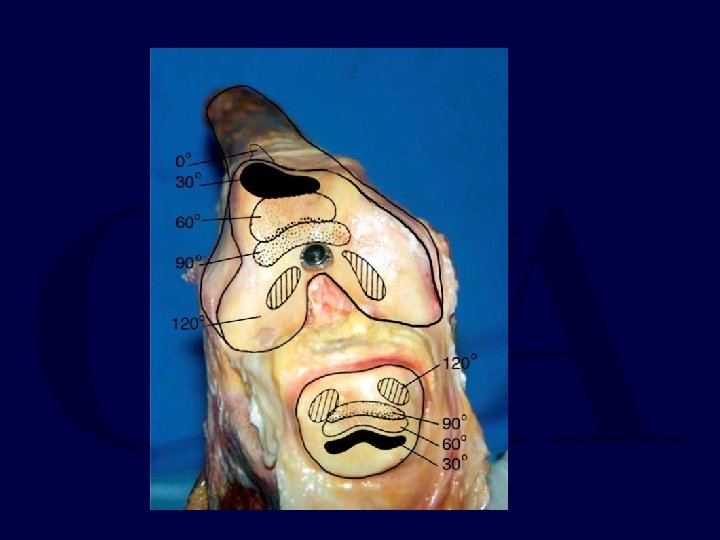

Mean Contact Area

Maximum Pressure * p < 0. 05 Only with the nail 1 mm prominent were the patellofemoral pressures increased

Retrograde Femoral Nailing • A cadaveric study using Fuji film demonstrated NO deleterious effects on the patello-femoral joint with a properly inserted retrograde IM nail • The orthopaedic literature does NOT support decreased knee motion or increase knee pain with a retrograde nail